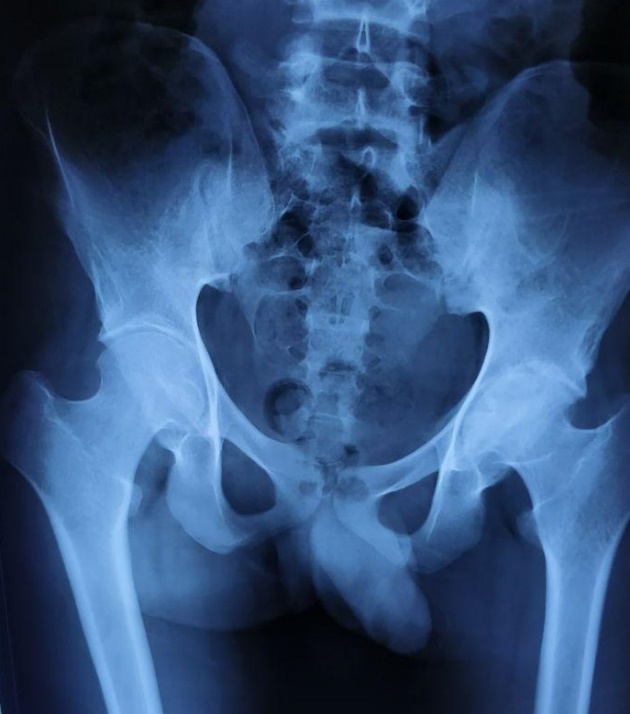

Coxa Valga and Caput Valgum

Coxa valga and caput valgum move the fovea upward into contact with the acetabular dome. Weight bearing on the fovea can cause pain from incongruity of the cartilage surfaces as well as from crushing of the ligamentum between the head and the acetabulum. Treatment is varus osteotomy to move the fovea medial to the sourcil.

Foveal loading from coxa valga — fovea in contact with the acetabular dome

Foveal loading from coxa valga — fovea in contact with the acetabular dome.